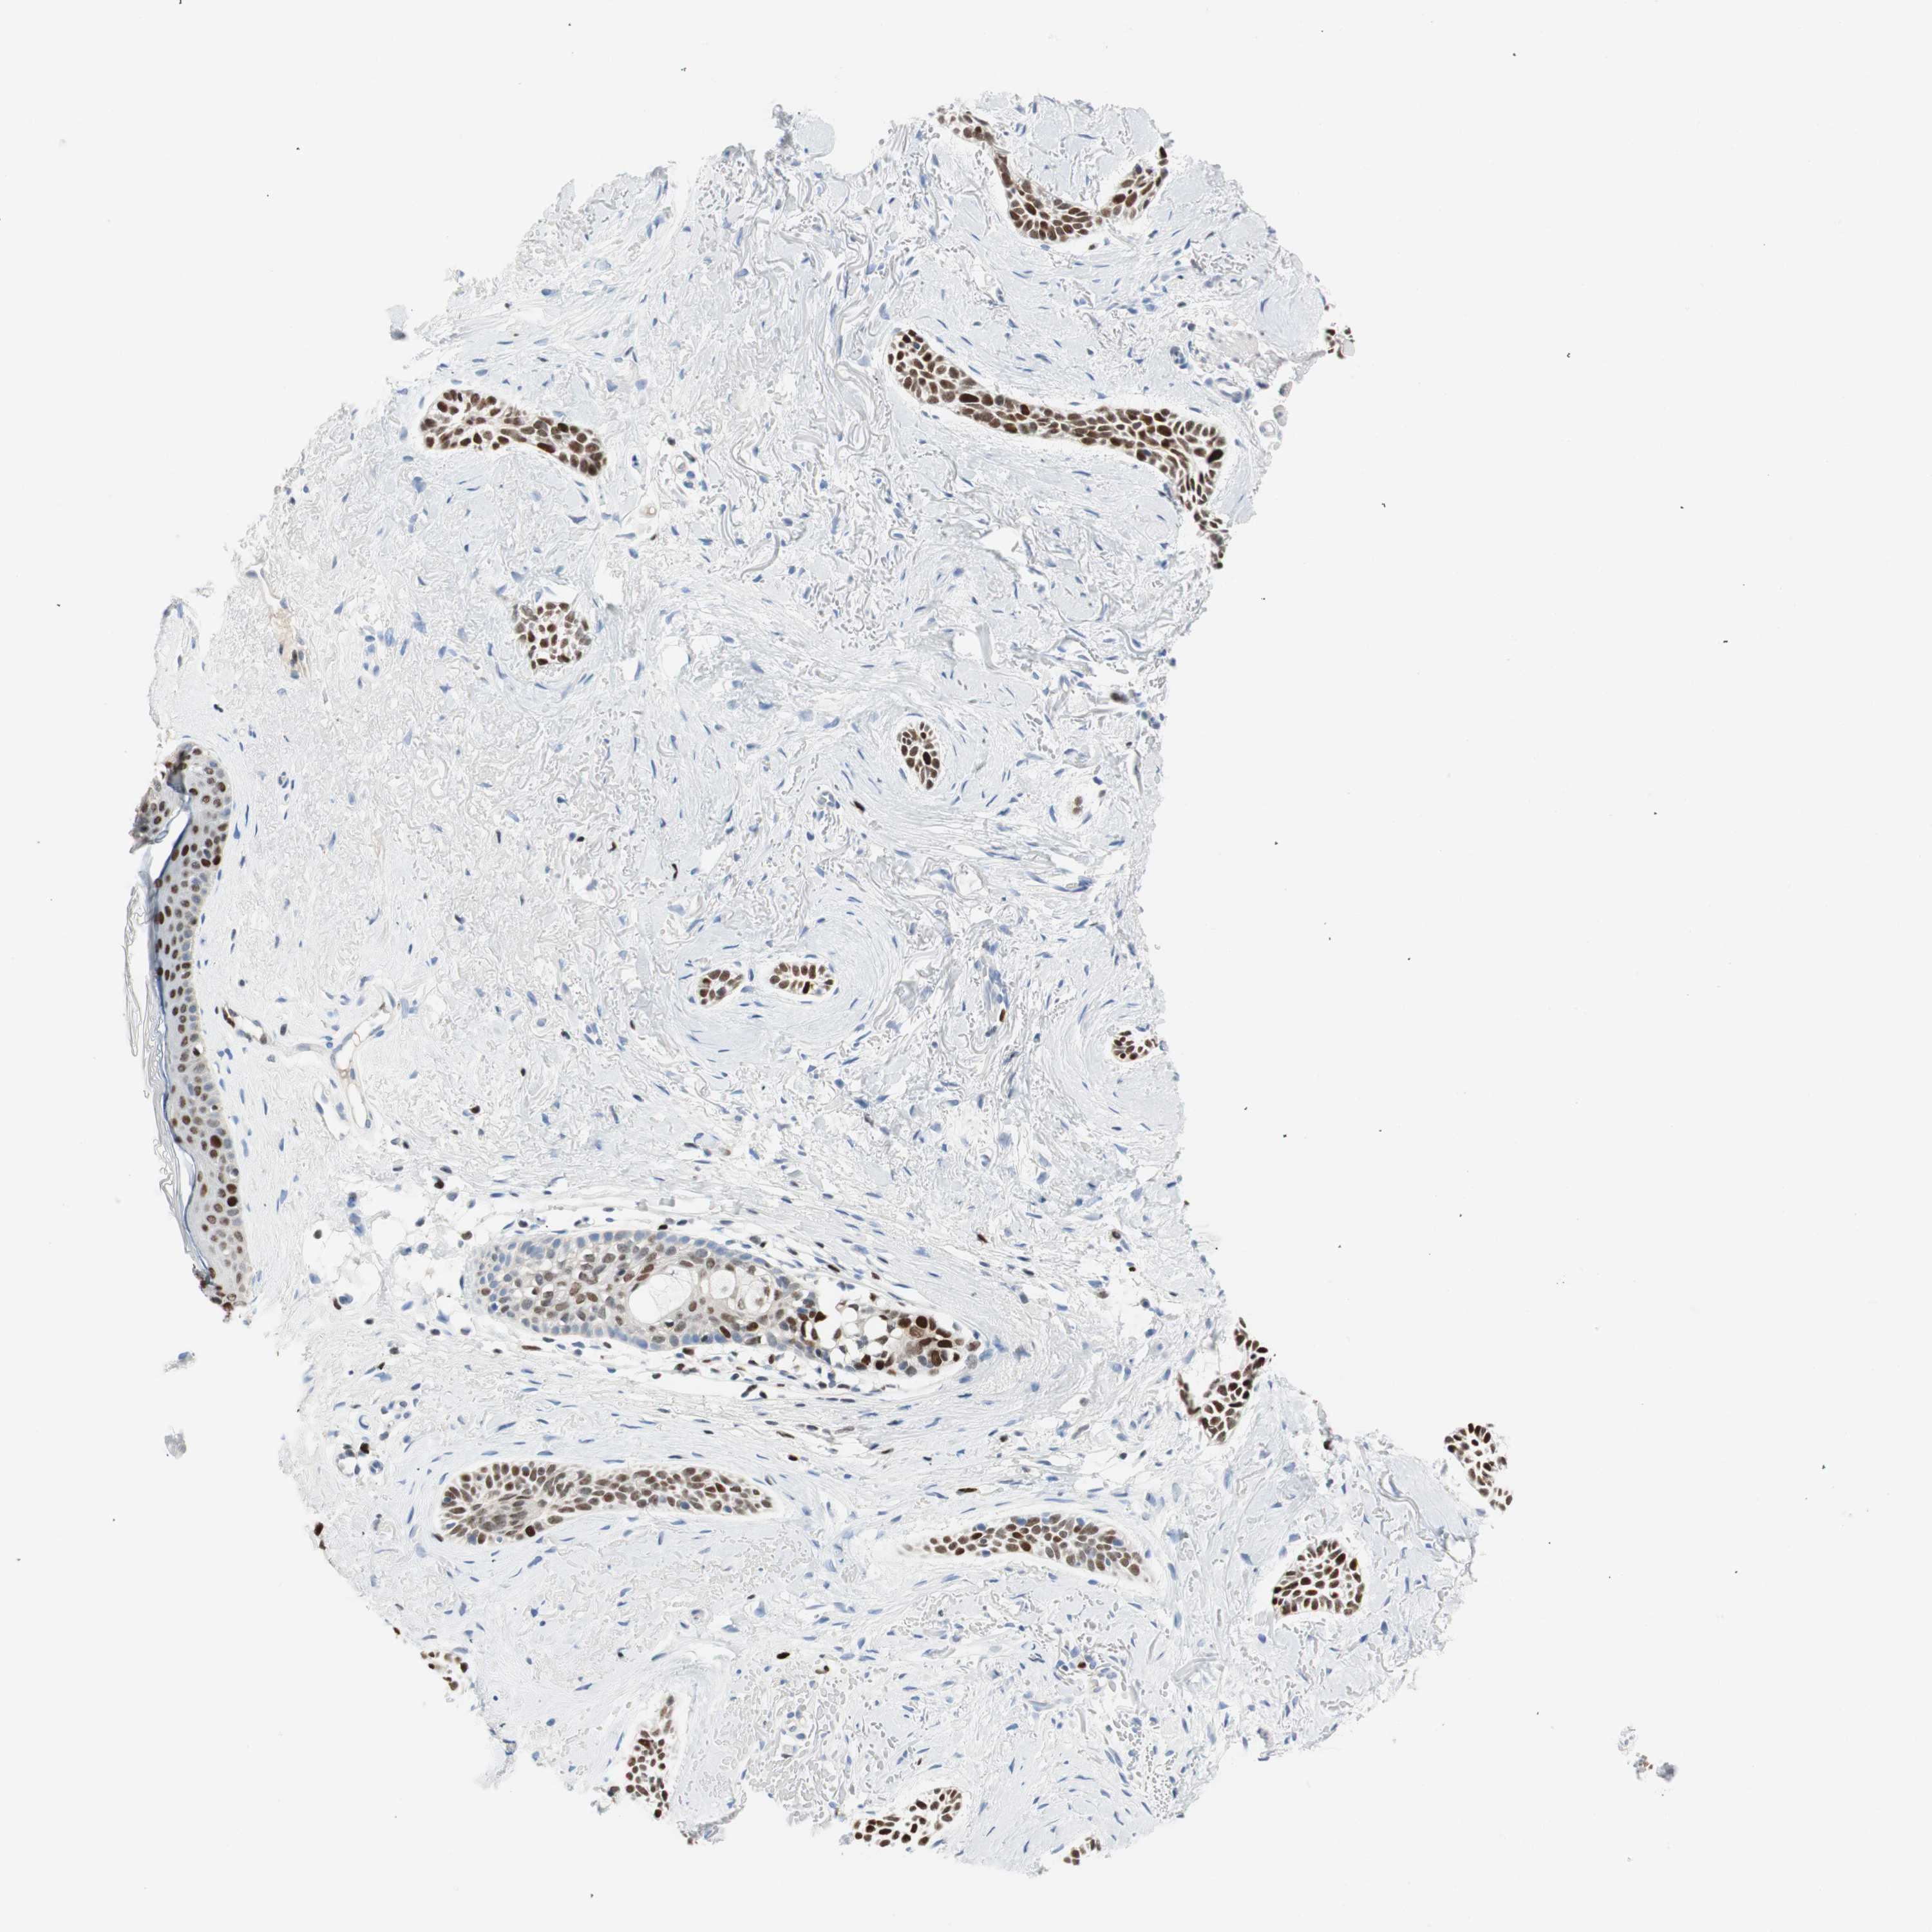

SKIN CANCER - Protein expressioni

A mouse-over function shows sample information and annotation data. Click on an image to view it in a full screen mode. Samples can be filtered based on level of antibody staining by selecting one or several of the following categories: high, medium, low and not detected. The assay and annotation is described here.

Antibody staining in the annotated cell types in the current human tissue is reported as not detected, low, medium, or high, based on conventional immunohistochemistry profiling in selected tissues. This score is based on the combination of the staining intensity and fraction of stained cells.

Each image is clickable and will lead to virtual microscopy that enables deeper exploration of all samples and also displays staining intensity scores, fraction scores and subcellular localization as well as patient and tissue information for each sample.

Antibody CAB009589

Basal cell carcinoma